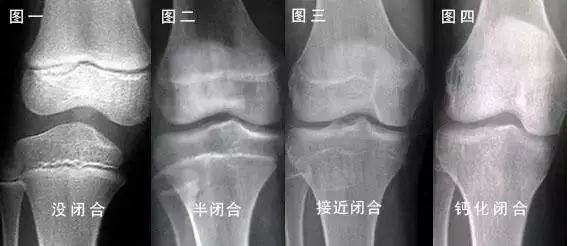

气化就是使物质发生变化,即新陈代谢,唯有在阳气的“气化”作用下,饮食水谷才能合成人体有用的物质充养人体,同时分化出无用的代谢废物排出体外。推动就是推动人体气血精津液正常循环,濡养人体,确保人体的生长发育一切正常。二是:春季紫外线含量在所有季节中最高(不是夏季)。而维生素D只有经过紫外线的照射,才能转化成维生素D3。进而转化成具有生物活性的羟化维生素D,以促进胃肠道对钙和磷的吸收,而钙和磷是骨骼生长发育的基础。 所以,把握住春天,就相当于把握住了孩子身高“逆袭”的黄金季节! 这条线就是骨骺线。人的身高,主要是长骨的增长体现的,长骨的最终长度决定了成年后的身高。多数情况下,只要骨骺线未闭合,就还有长高的机会;反之,当骨骺线闭合时,长骨也就不再生长了,人的身高也就基本定型了。 在骨骺线彻底闭合之前,有两个长高黄金期:3岁以内和青春期。这两个时期,骨骺线处于开启状态,长骨有足够的生长空间。 医学数据显示:女孩在10-12岁开始,男孩在12-14岁开始,年增长速度可以达到每年7-8厘米,快的可以达到10-12厘米。 所以,家长们一定要抓住这两个生长高峰期,通过科学干预,让孩子长高个儿! 中医讲,“肾主骨”,骨骼的健康发育是长高的前提条件,而骨骼的发育取决肾气是否旺盛。其次,脾为后天之本,脾胃的功能好才能给长个提供基础物质。